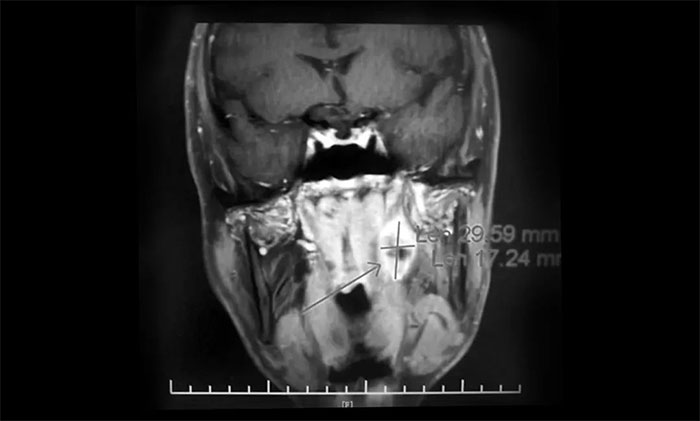

一位64岁男性患者,因“左颈部淋巴结肿大伴鼻出血半月”在外院行鼻咽镜活检病理结合影像学检查,提示鼻咽癌可能。为寻求进一步治疗近期来到我院。查MRI:左侧鼻咽部实性占位性病变,考虑恶性肿瘤,侵及左侧咽旁间隙;左侧下颌腺区及颈部淋巴结异常肿大(转移可能)。

▲ 入院MRI影像